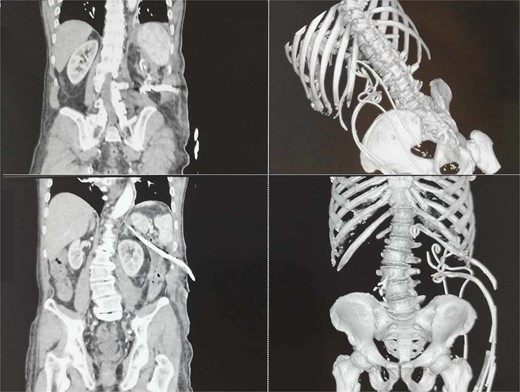

CT image of large infected peripancreatic collections with multiple air locules (A and B) and placed pigtail catheters post-imaging (C and D).

Following well-established guidelines, empiric antibiotic therapy with a carbapenem was started (Meropenem 1 g every 8 hours). The patient underwent PCD with the initial insertion of five drains: two in the peripancreatic collection and three in the pararenal space, with one situated caudal to the lower border of the collection at the level of the iliac crest. Microbiological examination revealed the presence of Meropenem-resistant Escherichia coli, sensitive to Cefoperazone-sulbactam, necessitating a change in antibiotic treatment according to antibiogram results. Continuous postprocedural transcatheter lavage with physiological saline was performed. Follow-up abdominal sonography showed the persistence of a small undrained collection in the posterior pararenal space, leading to the placement of two additional drains in that area (Fig. 1C and D).

A subsequent microbiological examination showed no bacterial growth. Normal laboratory findings. Additional abdominal ultrasound and CT showed no significant remaining fluid collections (Fig. 2).